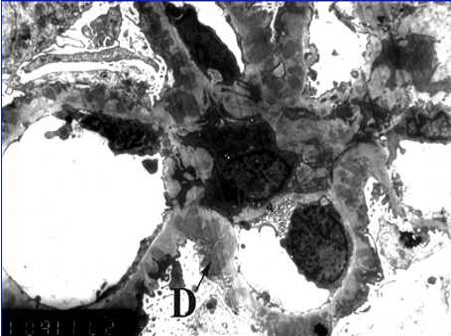

肾活检病理由于疾病具有独特的发病机制和特点,对病理技术要求很高,常规的HE染色需要薄切片,还要结合多种特殊染色(图1)、免疫荧光/组化(图2)及透射电镜检查(图3),才能进行正确诊断,为患者的治疗和预后判断提供依据。

图3,膜性肾病,电镜